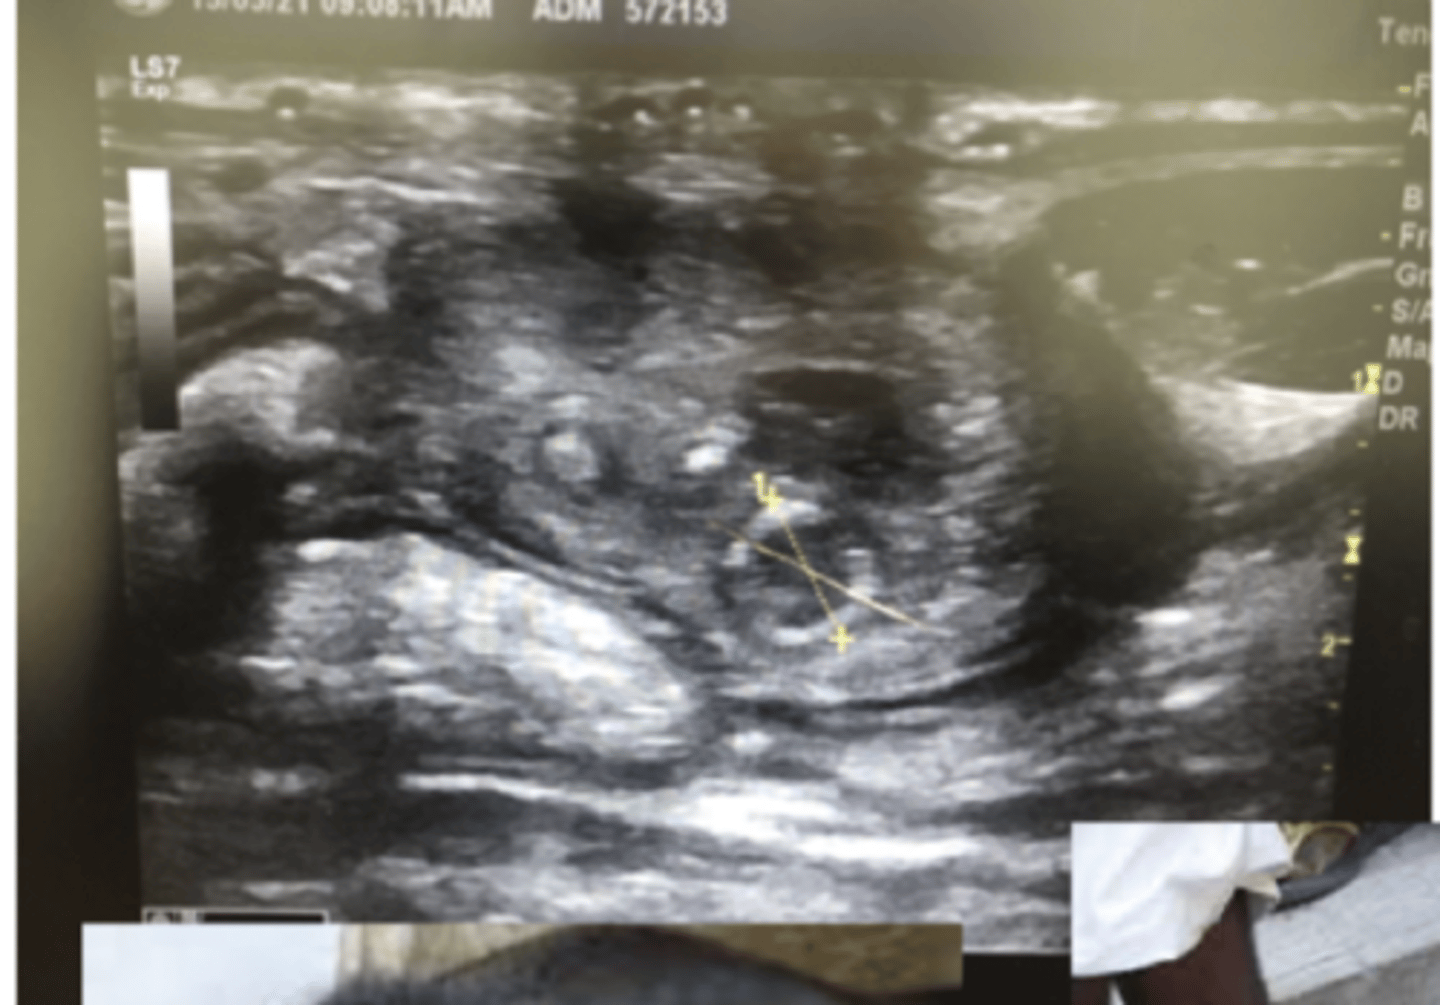

outcomes of failure of passive transfer of immunity 1

Internal umbilical remnant

enlarged right umbilical artery associated with infection

outcomes of failure of passive transfer of immunity 2

fibriosupprative ammonia, secondary to bacterial transfer after failure of passive transfer